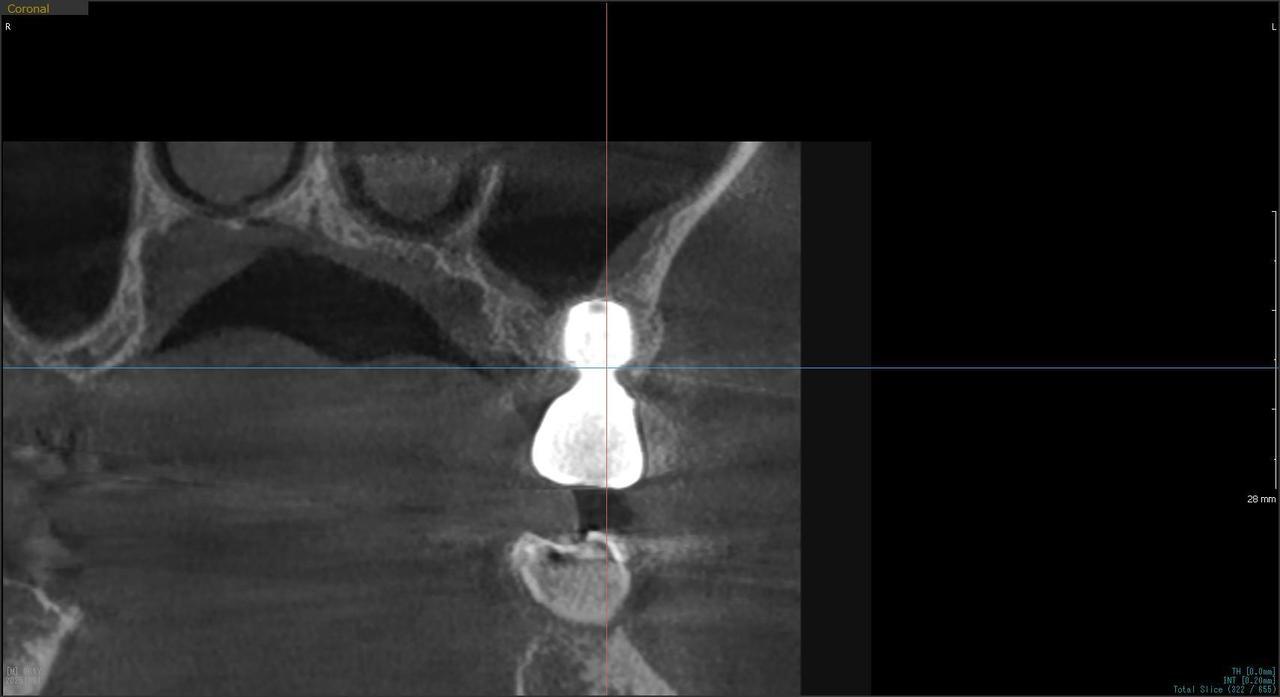

2.右上6番の上顎既存骨2mmのグラフトレスサイナスリフト(骨補填剤を使わない上顎洞挙上術)のケース

K・Y 様 女性 50代

症状としては、右上6番の歯が歯周病のため、自然に抜けてしまった。

治療法としては、歯周病により、右側6番の上顎骨が吸収して、2mm程度の骨しか残っていなかったため、サイナスリフトが必要であった。通常のサイナスリフトだと時間(時間的には1年から1年半程度かかると考えます。)と費用がかかり、患者様への時間的、肉体的、金銭的負担が大きくなることを考慮して、今回は、インプラントの種類としては、エクストラワイドショートインプラント、術式としては、デンサーバーを使用したグラフトレスサイナスリフトを選択しました。最終補綴物はジルコニアで仕上げています。

結果としては、高度に吸収した上顎骨に対するインプラント治療であったが、グラフトレスサイナスリフトを行うことで、短時間(2か月半程度)で治療を終えることができた。また、サイナスリフトによくある術後合併症である上顎洞炎を起こすことなく、患者様への肉体的な負担を抑えた治療を行うことができた。また、上顎右側6番にインプラント治療できたことにより、咬合が安定するとともに、歯周病にり患している上顎の他の歯に対する負担を少なくすることができた。

治療の期間・回数:約2か月半、6回

治療の価格:363,000円(税込)

治療費の内訳:インプラント基本料(フィックスチャー及び手術費用、投薬費用、レントゲン費用、インプラント上部費用(アバットメントおよびジルコニアクラウンの費用用)330000円(税込み)オプション費用グラフトレスサイナスリフト費用 33000円(税込み)

治療のリスクや副作用:手術後に、痛みや腫れ、出血、合併症などを引き起こす可能性があります。噛む感覚がご自身の歯と異なる場合があります。見た目がご自身の歯と異なる場合があります。手術後にメインテナンスを継続しないと、インプラントが抜け落ちる可能性があります。